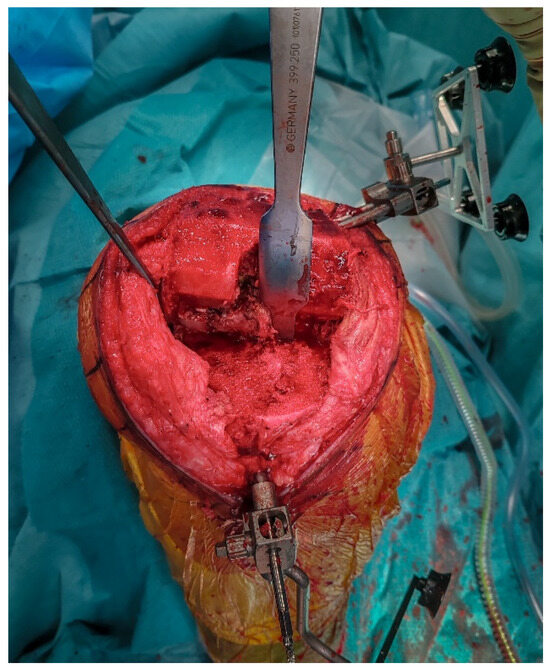

2.5. Implant Removal

The femoral and tibial components are removed using thin osteotomes and an oscillating saw, preserving as much bone as possible (Figure 4). Careful sequential release of the bone–cement interface, combined with minimal lever forces, helps reduce the risk of iatrogenic bone defects.

Figure 4.

Intraoperative view after removal of the medial UKA components, showing bone-sparing removal with preserved host bone.